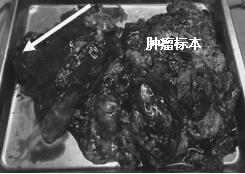

當(dāng)我們積極行術(shù)前準(zhǔn)備��,制定手術(shù)預(yù)案���,行手術(shù)時�����,麻醉科段雪琴主任并沒有因為病情危重�,插管困難��,氣管塌陷等可預(yù)見危險而停止手術(shù)�。相反,聯(lián)系呼吸內(nèi)科,共同行氣管鏡插管�,事實上,麻醉過程驚心動魄��,受壓的氣管幾乎導(dǎo)致插管失敗�����,持續(xù)的缺氧讓我們?yōu)椴∪松钅罅艘话押埂?BR>當(dāng)我們有條不紊地打開胸腔�,滿視野的腫瘤讓人汗毛倒豎,當(dāng)一點一塊切除腫瘤��,患者的癥狀逐漸緩解����,缺氧改善,生命體征趨于平穩(wěn)后�����,我們幾乎癱坐在凳上�,那緊繃的弦才稍有松弛。

當(dāng)看到病人癥狀緩解�,復(fù)查胸部CT幾近完美�����,我們那種自豪感油然而生�����。偶爾去治愈,常常去幫助��,總是去安慰�,我們深知,小伙子的人生之路并不長����,只能深深祈禱他在我們的治療下能走得更遠(yuǎn)一些,能把剩下的日子走的更充實一些����。而我們在能夠幫助人的時候�,別一味地去安慰,永不言棄���,是我們這一群胸外人堅貞的信念。